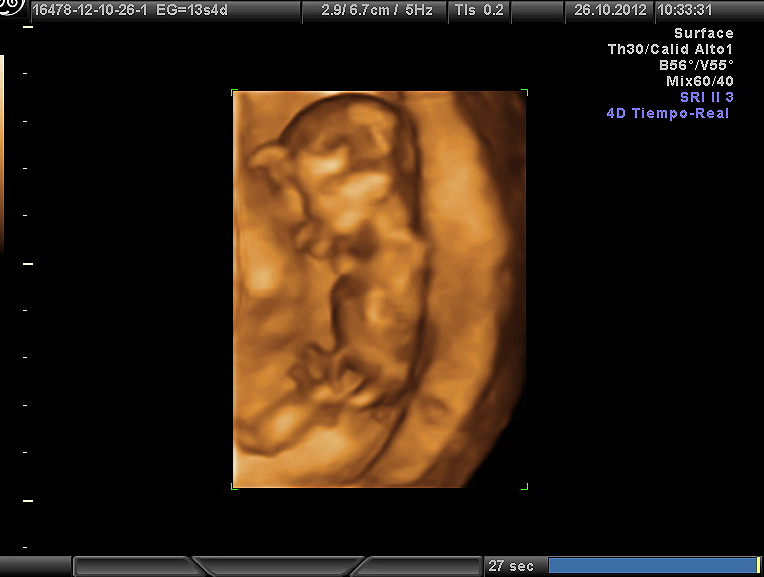

Cuando hicimos la primera eco, temblábamos como dos niños que pequeños que no quieren que les quiten la ilusión, sabemos los riesgos que nos aporta la edad, pero la vida siempre se abre paso entre los datos y las estadísticas. Naia nos deleitó con un no parar de movimientos, pataleaba como su hermana en la cama, y se restregaba los ojos incipientes en señal de sueño para que no la despertáramos.

La eco resultó perfecta, su corazón latía con mucha fuerza, con la misma con la que no paraba de moverse, con la misma que nos transmitía a nosotros a cada golpe de latido.